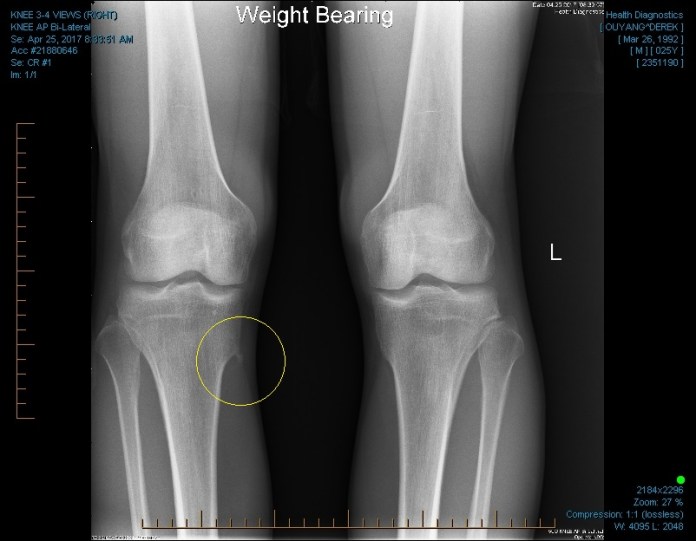

On August 3, I had surgery to remove an osteochondroma, which is a small bone mass that occurs in 3% of the population and usually shows up near joints like knees and elbows. Mine was just below the knee on the proximal tibia and was shaped like a hook, as you can see in this X-ray image.

In 2007 or so, probably somewhere on the football field during marching band practice, my left leg locked for the first time. A few days later, a second doctor noticed something odd on the standard X-ray; on the bottom corner of the image, away from the actual knee region where the previous doctor had focused his inspection, this doctor noticed a strange hook shape right where the tibia narrows from the knee to the long, slender section of the bone (just as I showed above). As he demonstrated, this hook was snatching a specific set of ligaments as they passed over the ridge during bending. Now that I was focused on the right place, I could literally feel it happening under my fingers, like a buckle snapping shut. Suddenly, it became clear that the previous surgery had been pointless, that the source of the locking was still present on both knees, and that the only solution was to actually go in and shave off the hook. I remember feeling nowhere near as curious or fascinated about my predicament; rather I felt the first tinges of a deep melancholy, the kind that I suspect permeates old age, as the unfortunate surprises of our genes all come out into the limelight. It was an early warning sign of the facts we cannot change, the consequences with no one to blame.